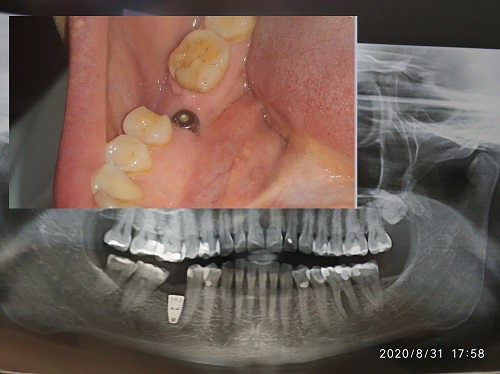

I had implant placed 3 months ago (molar 36). After surgery implant was hidden below gums. Last week a healing cap was placed and I started to wonder if this placement is correct. Isn’t it too close to adjacent tooth and too close to buco lingual side? I’ve decided on implant after almost 15 years of missing tooth. Is my implant incorrectly placed? What are threats to failure of keeping it this way? Please advise.

it's nothing to brag about but it will work. much rather have it too far lingual than too far facial . too close to 29 yes but as long as 29 pulp tests ok then don't worry. This is a case where an angled stock abutment is pushed to the limits and a custom abutment will work. next time take more time. if you are right handed this should not have occurred as visibility allows placement freehand to within less than 1mm. next time do you test X-ray just barely into cortical bone to get your site selection and angulation. you were distracted and falling behind schedule when you did this because you weren't worried about the mental foramen you though it would be a slam dunk and it fooled you

The implant probably was placed in its lingualized position because of atrophy of the alveolar ridge at the expense of the buccal bone. Such bone loss is to be expected when the tooth has been missing for so many years. And yes, the implant is woefully too close to the premolar. These deficiencies will lead to all sorts of problems during and after when it comes to placing an abutment and crown. This implant should be removed, the ridge augmented, with later placement of an implant in the proper position. Or, a fixed bridge is a reasonable alternative if you don’t want to proceed with the above. Also, it is wise to use a surgical guide even when placing a single implant in a site such as this. This helps preclude sometimes unforeseen problems. (PS: #46 looks like it is need of attention.)

The implant was placed in the position that the gap for the crown allowed. Actually pretty accurate placement. The alternative would have been to prosthodontically or orthodontically upright the second molar, reduce the overeruption on the opposing tooth and then place the implant in the ideal position. A normal stock standard straight abutment will work, but your concern always will be food impaction to the distal and subsequent bone loss. Make sure good oral hygiene is followed and monitor this 6 monhly.

Take some courses in guided bone regeneration. Look over the apposing teeth....looks like there could be decay. A 4.3mm x 8mm should keep you well away from the IAN.